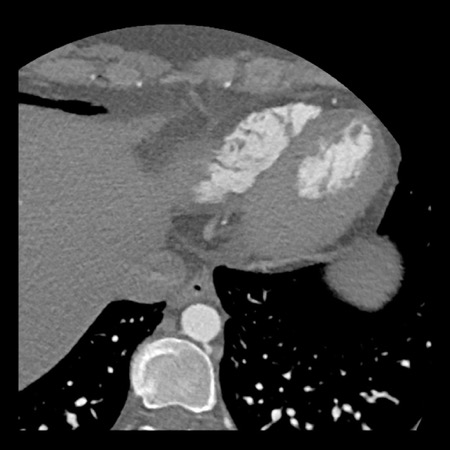

Continue with the next images…

A: ICA correlates with CTA and shows an 80% stenosis in the mid LAD

(white arrows) and a 60% stenosis in the D2 branch (black arrows). The D2

stenosis was overestimated on CTA.

B: PCI was performed during which a drug eluting stent (DES) was

implanted with good results (white arrows).